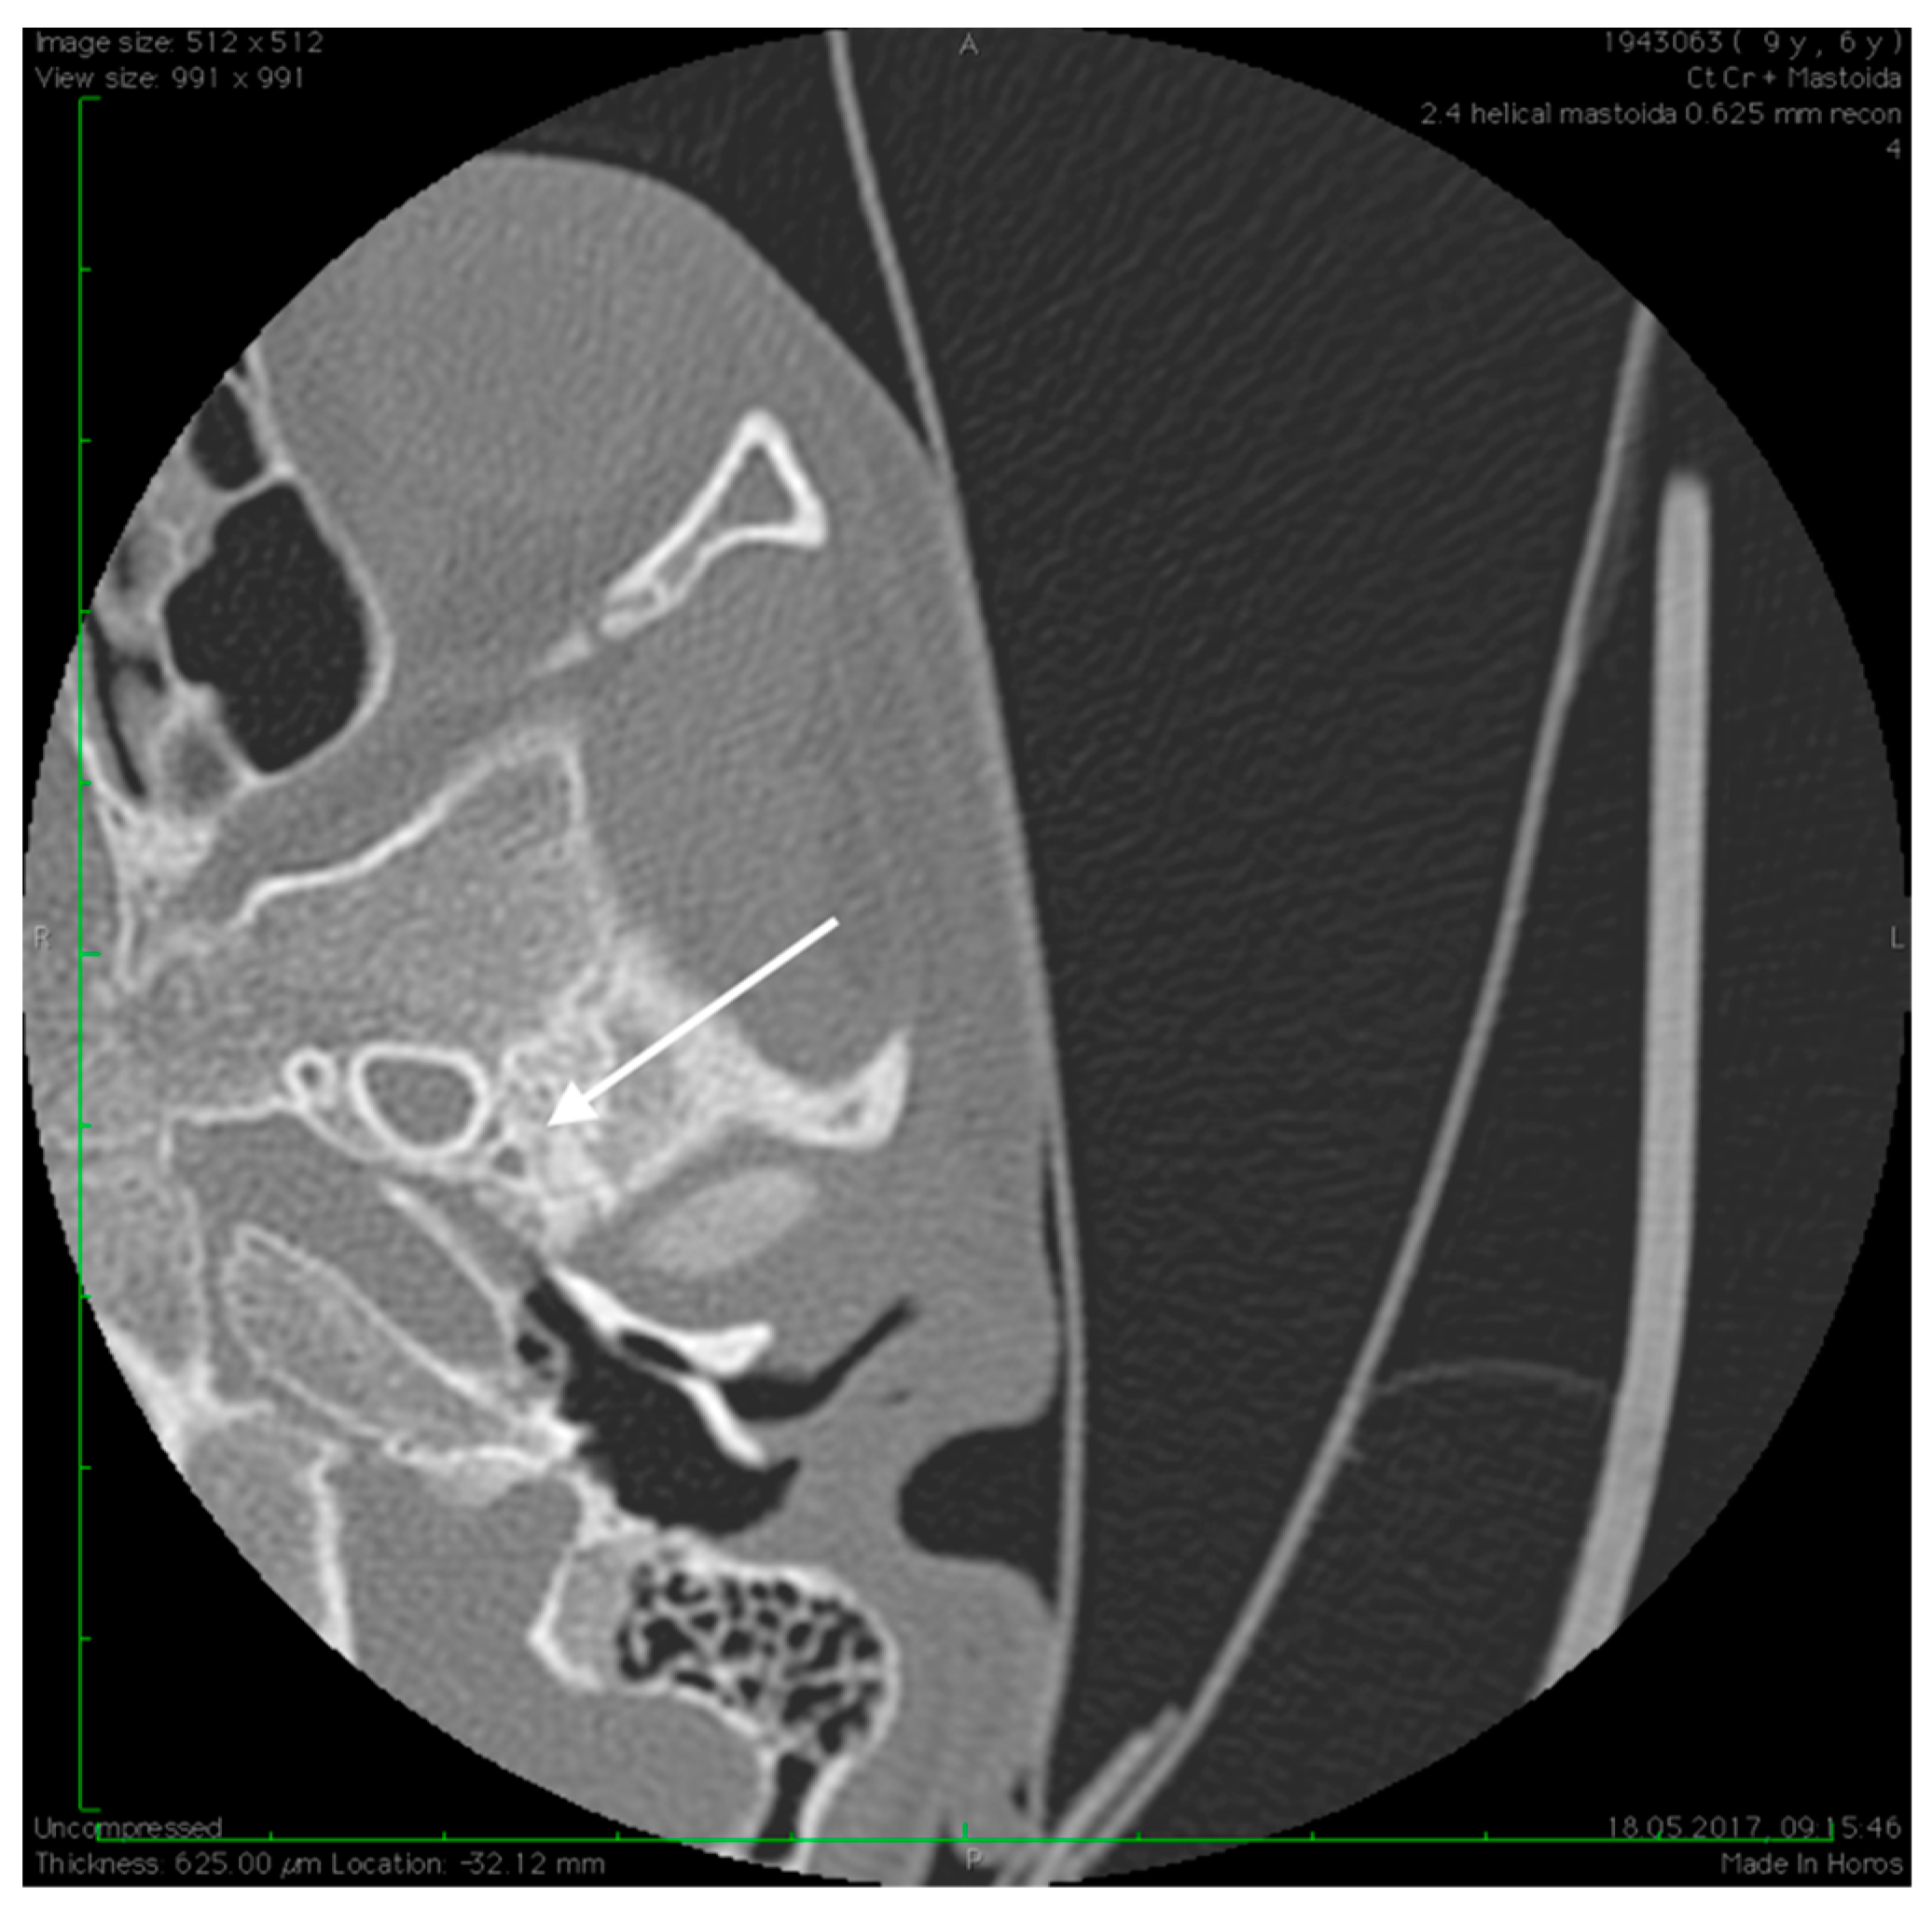

Figure 6.

Abnormal position of the facial nerves in their mastoid segment, bilaterally (arrows).

No family history of hearing problems could be elicited. A high resolution CT scan revealed bilateral middle ear anomalies. There were no images of the oval window and stapes suprastructure in his left ear, with abnormal facial nerve canal position and patent foramen spinosum (Figure 2 and Figure 3). The stapes suprastructure and the oval window were also missing to the contralateral (right) ear with a wide facial nerve canal between the geniculate and the round window niche and an abnormal traject on its mastoid segment. No foramen spinosum was observable on the right side (Figure 4, Figure 5 and Figure 6). Furthermore, surgery was carefully planned to investigate the middle ear.

Preoperative CT imaging of middle ear surgery patients is mandatory and careful interpretation of the results can sometimes prevent accidental injuries brought to a PSA. The usual findings are a small, abnormal, canaliculus leaving the carotid canal or the facial nerve, a straight line structure crossing over the promontory, an unusual widening of the fallopian canal or a different canal parallel to it between the geniculate and the oval window niche and absence of the foramen spinosum []. Our CT findings coincide with some of the aforementioned signs, as there can be seen no trace of the foramen spinosum in the affected ear (Figure 5), in contrast to the contralateral ear (Figure 3). There is also a widening of the facial nerve canal that can be observed in Figure 4. It came as no surprise that the stapes could not be described in the CT images, as the literature review acknowledges the possible stapes malformations that come along with PSA.